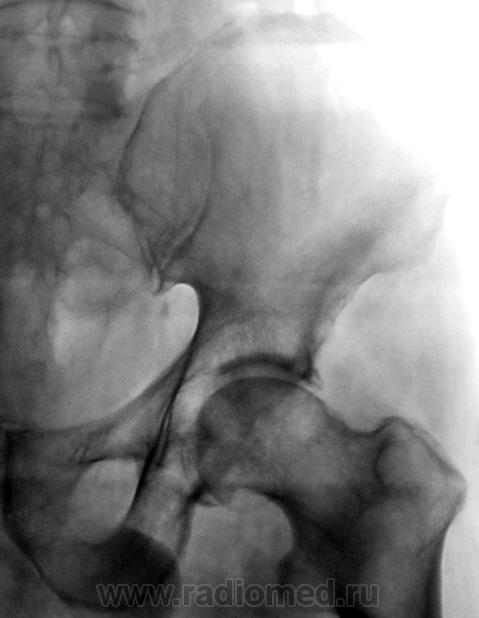

В принципе, болеть есть от чего. Однако, у меня на подозрении очаги разрежения структуры в головке левой бедренной кости и в теле правой подвздошной кости над вертлужной впадиной. Очаги весьма четкие, круглые - дообследуйте на предмет миеломной болезни.

Бластического варианта НЕТ. Очаги просветления, в данном случае -затемнения газ в к-ке. ДОА пр.т/б сустава 4 , левого - 2 степени, артрозные изм-я в сакроилеальных сочленениях, выраженней в левом

Правая половина таза меньше за счёт проекционного искажения?

Да, положение вынужденное.